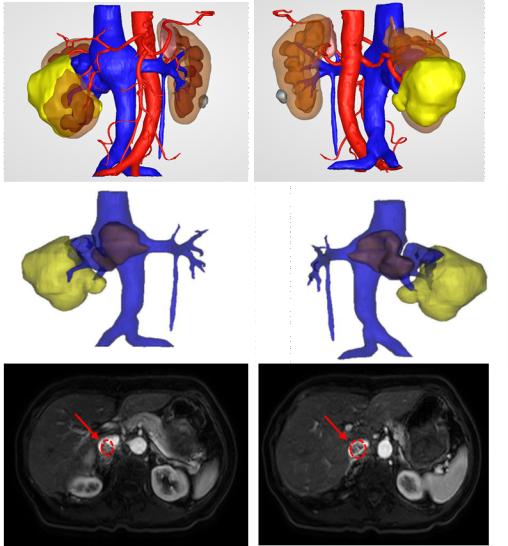

(3D重建显示肿瘤与周围器官的关系)

(肿瘤、癌栓与肾静脉的关系)